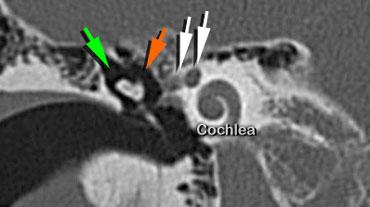

Scutum (mũi tên vàng). Đầu xương búa (mũi tên cam) được thấy nằm phía trong so với xương đe (mũi tên xanh lá)

Scutum

Scutum (mũi tên vàng) là một gai xương nhọn được tạo thành bởi thành ngoài của hòm nhĩ và thành trên của ống tai ngoài.

Bên trái, điểm trước nhất của dây thần kinh mặt được thấy (mũi tên trắng).

Tại điểm này, dây thần kinh tạo thành vòng chữ U.

Vị trí này được gọi là genu hay geniculum và đại diện cho hạch gối (geniculate ganglion).

Một lát cắt coronal hơi ra phía sau hơn sẽ cho thấy dây thần kinh mặt hai lần.

Phần phía trong là đoạn thoát ra khỏi ống tai trong và chạy về phía hạch gối (mũi tên trắng phía trong).

Phần phía ngoài là đoạn chạy theo hướng ra sau, xuất phát từ vòng chữ U của gối thứ nhất.